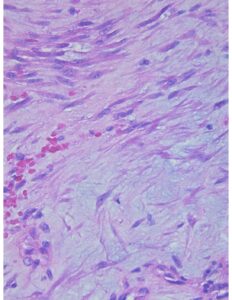

Los Fibroblastos Tumorales: ¿Los Vecinos Indeseables del Microambiente Tumoral?

El término fibroblasto (FB) y su descripción detallada se atribuyen a Karl Langerhans en 1870. [...]